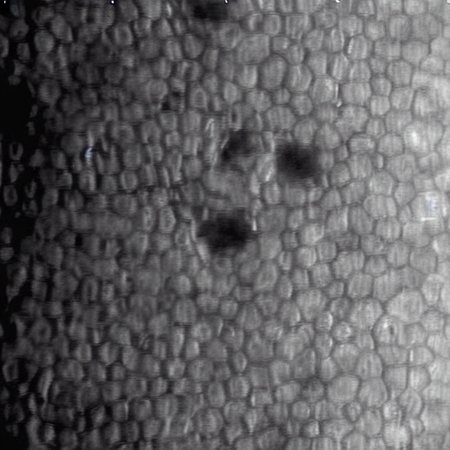

This LoRA generates photomicrographs of corneal endothelial cells in specular microscopy style (grayscale).

Cells with Guttata: Characteristic dark spots/drop-like lesions indicative of endothelial stress or dystrophy.